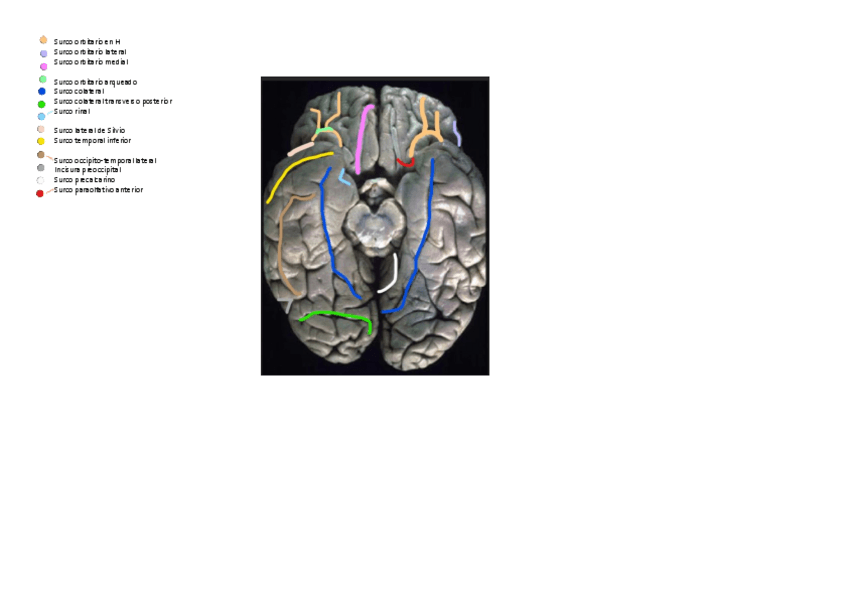

Surcos-cerebro-simulador-2023-24.pdf